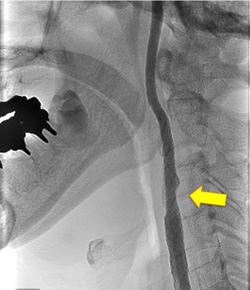

写真左:頚動脈狭窄所見

写真右:ステントを用いて狭窄部を拡張し治療